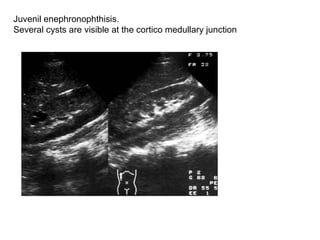

Juvenil enephronophthisis.  Several cysts are visible at the cortico medullary junction